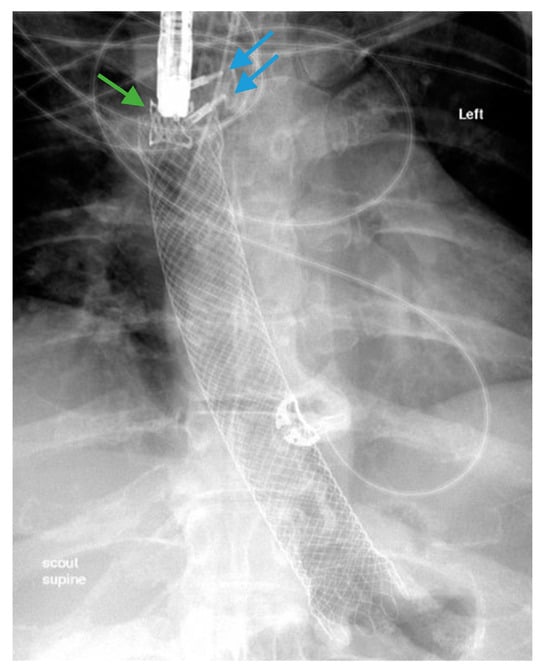

Scheme 7.

Gastric sleeve stenosis in the patient depicted in Scheme 5 was treated with through-the-scope balloon dilation to 20 mm as demonstrated on fluoroscopic image (arrow, left) and upper endoscopy (arrow, middle). Endoscopic contrast injection following dilation revealed improvement in the stenosis and flow of contrast (arrow, right). Note a small residual drain (green arrow, left).

Scheme 8.

Contrast injected endoscopically reveals a sharp angulation and stenosis of the sleeve in a patient following sleeve gastrectomy (blue arrow, left and top right). A pneumatic balloon dilation (green arrow, top right) was performed to 35 mm. Endoscopic contrast injection reveals no post-dilation leak of contrast (bottom right).